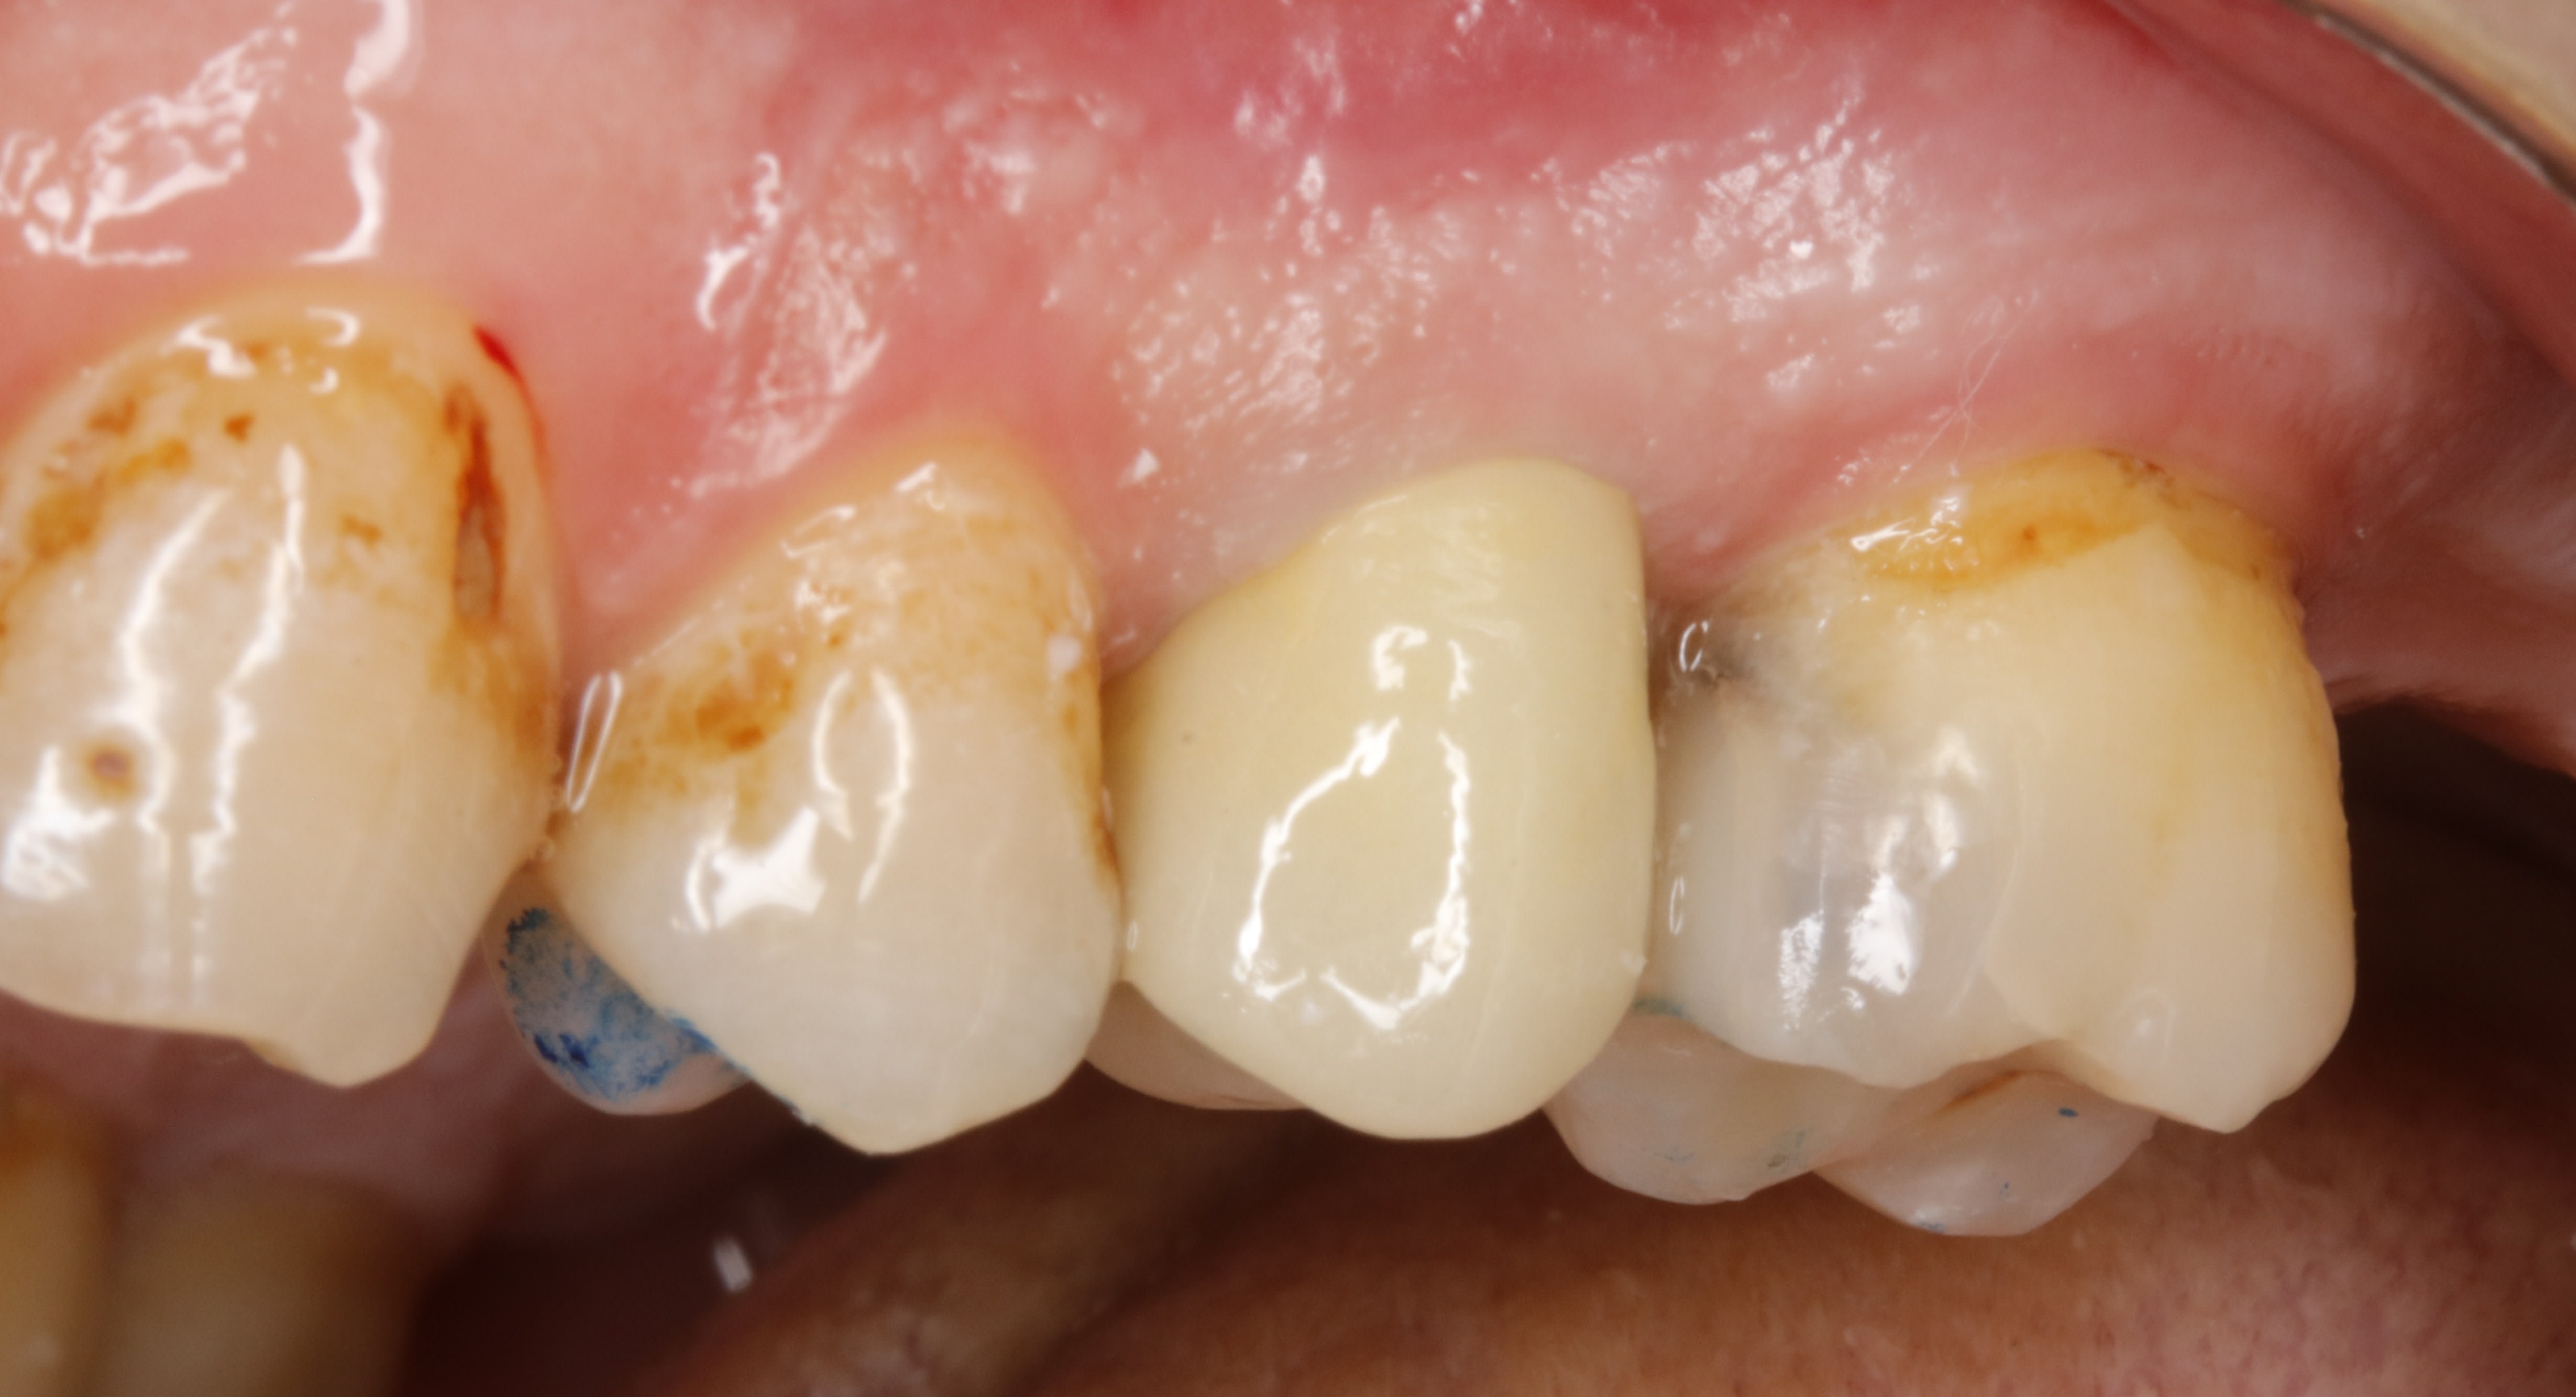

voilà , ce matin on est donc à 1 semaine .

on voit que la gencive ç est tassée .

je dis tasseé pcq on ne peut pas dire cicatrisée puisqu on ne l avait pas touché la semaine passée .

on peut mettre 1 fil , et meme se servir du chausse pied , ça ne saignera pas , ç est du beurre .

et on reprecise les limites à la grain fin .